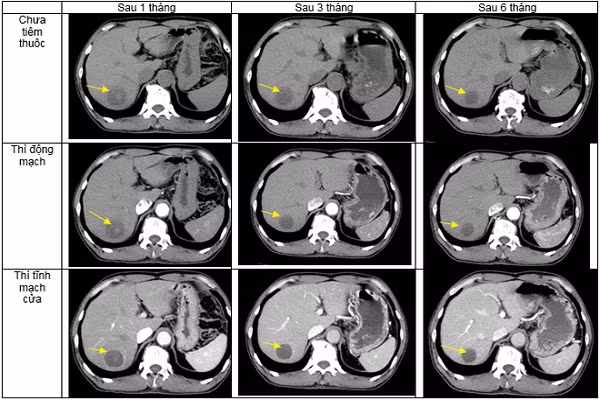

Bệnh nhân được đánh giá đáp ứng điều trị sau một tháng, sau 3 tháng và sau 6 tháng. Sau điều trị, triệu chứng cơ năng của bệnh nhân cải thiện nhiều, bệnh nhân ăn ngủ tốt, tăng 3kg, không còn đau tức hạ sườn phải.

![]() |